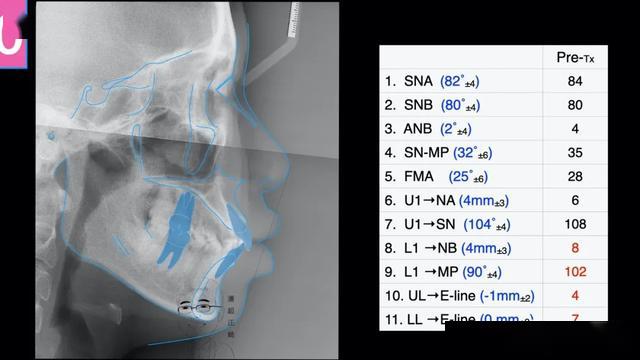

大赛一等奖正畸病例分享:微种植体支抗辅助矫治成人骨

的协调比例头影侧位片测量分析㈩ 上下中线正;㈨ spee曲线深约3mm;㈧

上牙弓拥挤2mm;下牙弓拥挤0.5mm 2.spee曲线深度:左侧1mm;右侧2mm 3.

覆盖5mm,覆合3mmspee曲线深约1mm,前牙bolton比:78%,全牙bolton比:92%